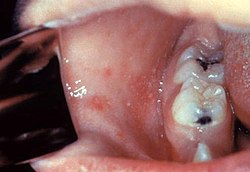

Typisch für die Masern ist ein zweiphasiger Krankheitsverlauf: Auf die Inkubationszeit von 8 bis 10 Tagen folgt das drei bis sieben Tage[92] dauernde, uncharakteristische Prodromalstadium, auch Initialstadium genannt. Dieses äußert sich durch eine Entzündung der Schleimhäute des oberen Atemtraktes (Katarrh mit Rhinitis), teilweise auch des mittleren Atemtraktes als trockene Bronchitis, sowie der Augenbindehäute (Konjunktivitis). Das Beschwerdebild in diesem Krankheitsstadium wird daher auch mit den Worten „verrotzt, verheult, verschwollen“ beschrieben. Dazu kann es zu Fieber bis 41 °C, Übelkeit, Halsschmerzen und Kopfschmerzen kommen. Die nur bei Masern vorkommenden Koplikflecken an der Wangenschleimhaut gegenüber den vorderen Backenzähnen (Prämolaren) sind eher selten zu beobachten und werden von manchen Autoren zu den atypischen Zeichen einer Maserninfektion gezählt.[93] Diese weißen, kalkspritzerartigen Flecken auf gerötetem Untergrund sind 1–2 mm groß und treten kurz vor dem Erscheinen des späteren Ausschlags auf.

Die Körperabwehr beruht vor Beginn des Exanthems vor allem auf dem zellulären Immunsystem (zytotoxische T-Lymphozyten, natürliche Killerzellen). Patienten mit einer verminderten Immunität, die auf einer Schwächung dieses Teils des Immunsystems beruht, haben ein hohes Risiko für eine Maserninfektion, die einen schweren Verlauf nehmen kann. Eine Immunschwäche, die sich auf den Bereich des humoralen Immunsystems beschränkt, führt hingegen nicht zu einem erhöhten Erkrankungsrisiko. Für die Entwicklung der typischen Rachenrötung (das von dem späteren Gerichtsmediziner Wilhelm Reubold (1827–1917), einem Doktoranden von Franz von Rinecker, 1854[90] erstmals beschriebene Enanthem, als Koplik-Flecken oder Kopliksche Flecken benannt nach dem Kinderarzt Henry Koplik (1858–1927) vom Mount Sinai Hospital in New York)[91] sowie Hautrötung (Exanthem, s. u.) spielen Immunreaktionen in kleinen Blutgefäßen (Kapillaren) eine wichtige Rolle. Daher können diese Zeichen bei immungeschwächten Patienten fehlen (weiße Masern), obwohl ein schwerer Krankheitsverlauf vorliegt. Mit Beginn des Exanthems setzt die Bildung von Antikörpern ein, zuerst der Klasse IgM, später auch von IgG.[89]